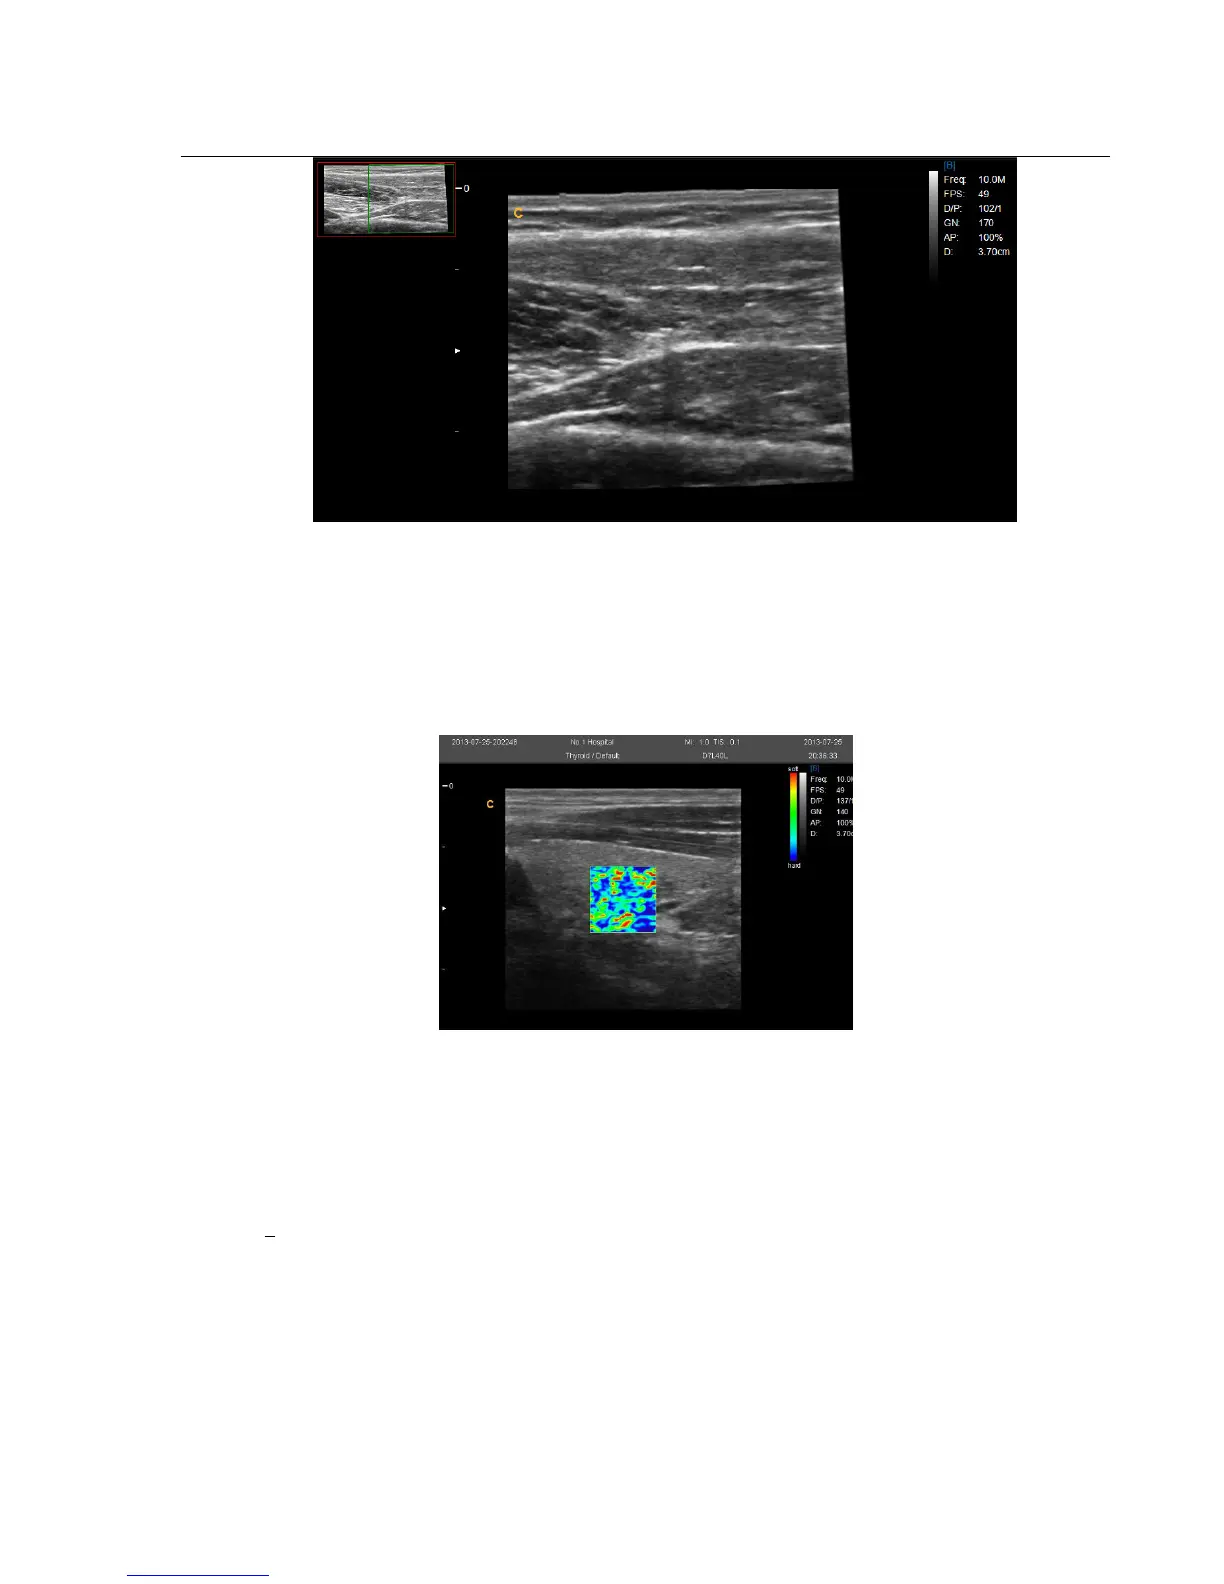

4.3.16. Elastography mode

Ultrasound elastography is a new ultrasound technology to study traditional ultrasound can not detect tumors and

spread of disease imaging, can be applied to the breast, thyroid, prostate and other aspects.

In B mode, turn elastography menu on can enter into elastography mode.